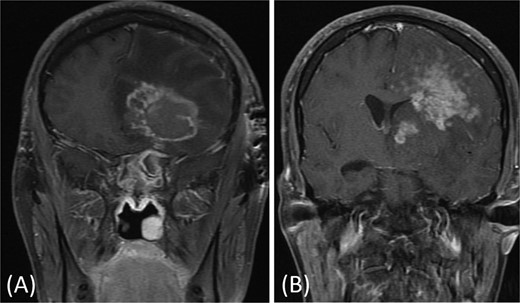

A previously healthy 36-year-old man presented to the emergency department complaining of persistent frontal headache, dizziness, and vomiting of 1 month duration, with no history of orbital complaints (e.g. visual deficits or swelling) or neurological deficits (e.g. limb weakness or seizure-like movements). On examination, the nasal endoscopy showed dry crusts filling the right nasal area. Therefore, due to the subtle symptoms’ origin, the patient was admitted, and a computed tomography (CT) scan of the head and a magnetic resonance imaging (MRI) of the brain were scheduled. The head CT scan revealed complete opacification of the maxillary, ethmoid, frontal, and sphenoid sinuses with bone destruction affecting the left lamina papyracea and roof of the ethmoid air cells (Fig. 1A). The brain MRI demonstrated similar findings with intra-orbital extension resulting in left global proptosis, which triggered concerns regarding fungal rhinosinusitis (Fig. 1B). Accordingly, the patient underwent functional endoscopic sinus surgery (FESS) with a right frontal craniotomy and partial removal of the infected brain tissue on the fourth day of his presentation. Specimens from both surgical sites were sent for pathology and cultures during the surgery. The histopathological results confirmed the diagnosis of CGIFRS, and A. flavus was found in the tissue culture. Postoperatively, the patient was stable, and intravenous antifungal treatment (amphotericin B and voriconazole) and high-dose steroid administration (dexamethasone) were started promptly following confirmation of CGIFRS via pathology. One week after the surgery, the patient’s condition suddenly deteriorated: he had a right fixed dilated pupil and spikes of fever. An urgent brain MRI with contrast was performed, which showed an intracranial abscess, and a significant midline shift to the right side (Fig. 2A and B). The patient, therefore, had a right decompression craniotomy and remained intubated and ventilated in the intensive care unit to receive the maximum medical therapy. However, despite this intensive treatment, the patient’s condition continued to worsen, and he ultimately died after 2 weeks.

(A and B) Brain MRI with contrast showing signs of intracranial abscess in the left side with mass effect and midline shift to the right side.